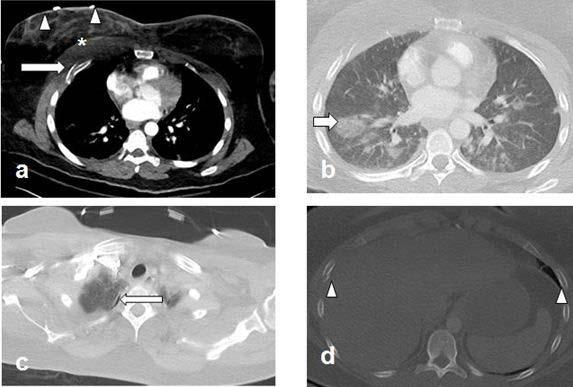

"During the pandemic, victims experienced more injuries to the chest and abdomen compared to prior years," said coauthor Babina Gosangi, M.D., assistant professor of radiology at Yale New Haven Health in New Haven, Connecticut, and former emergency radiology fellow at Brigham and Women's Hospital. "For instance, one victim sustained multiple bilateral rib fractures with right pneumothorax and bilateral lung contusions--requiring hospital admission for more than 10 days--after she was repeatedly punched in the chest. Another victim was stabbed in the abdomen and had lacerations to the liver and kidney."